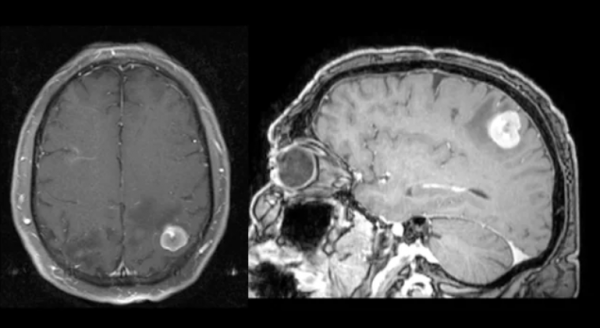

患者女,65歲,因進行性頭痛、右臂麻木2個月就診。MRI顯示左頂葉腦腫塊增強伴周圍血管源性水腫。胸部CT掃描發現毛刺狀肺腫塊。

肺癌患者中腦轉移很常見,與全腦放療(WBRT)相比,切除非小細胞肺癌(NSCLC)患者的孤立性腦轉移可提高生存率並改善生活質量。立體定向放射外科(SRS)聯合WBRT已證實NSCLC的生存獲益相似。SCLC所致的腦轉移瘤對放療高度敏感,與單純放療相比,手術切除尚未發現影響生存率。